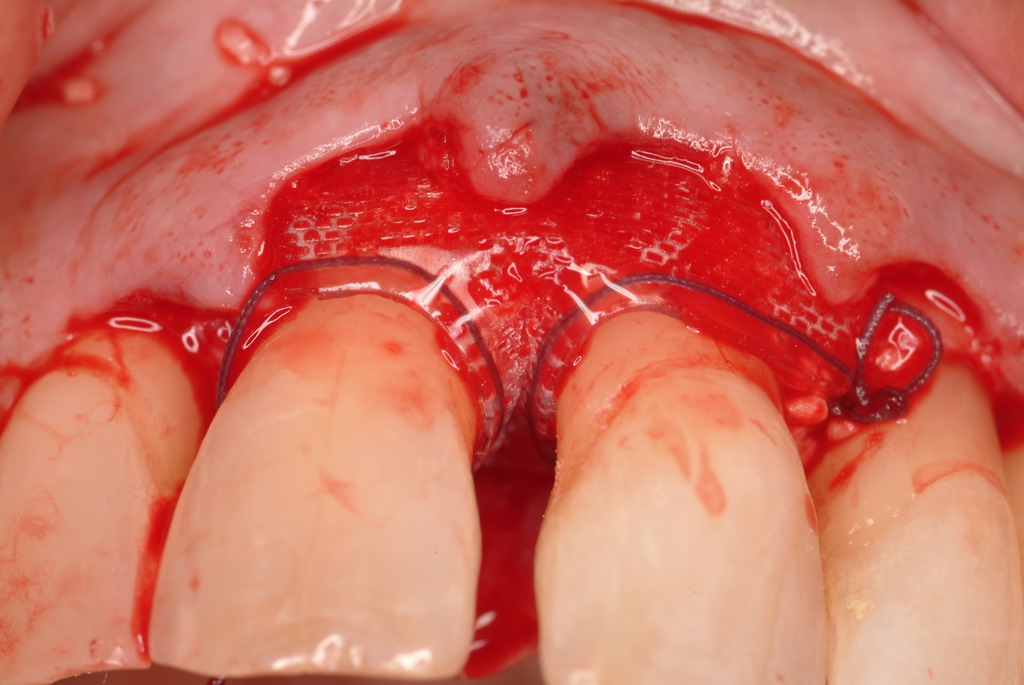

The patient had been referred for an implant consultation for the mandibular right canine. She had very deep probing depths on the lingual. When the flap was raised, a significant amount of subgingival calculus was seen as a local risk factor (Figure 18). However, she had no significant pathology to remove from the situation. Debridement was performed the same as in Case 3 with the rotary ultrasonic and manual instrumentation.

The defect was obturated with mineralized freeze-dried bone and hydrated with platelet-derived growth factor. As with any growth factor, when implementing it clinically, all growth factors require a carrier to bring that growth factor to the desired site, which do not elicit an inflammatory response. In this situation, it is the mineralized freeze-dried bone allograft. This combination was demonstrated by Rosen et al8 to be efficacious in treating intrabony defects. A biologic approach was taken both in terms of the graft and membrane (Figure 19). Primary closure was achieved.

A resorbable membrane sutured around the teeth bordering the intrabony defect.

Figure 15